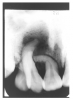

In Figure 4, recurrent caries appears at the mesial of tooth #3 and #4, and the distal of tooth #28. Also, note areas of interproximal caries on teeth #5-6.

Figure 4 - Recurrent Caries

Figure 4